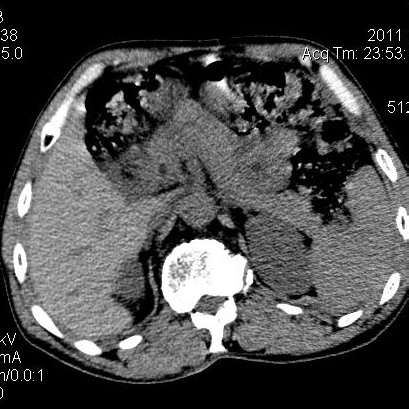

肝左叶发育异常

男性,55岁,骑摩托车摔倒后入院,自述右上腹疼痛

[backcolor=#FF0000]第一次诊断的时候也是这么肯定,可是床旁超声检查并没有发现明显异常,而且患者的一般症状都良好。还好临床只是保守治疗,没有立即手术,第二次复查的时候没有一点变化,又做了MRI检查,没有血肿,

这是一例肝左叶发育异常的,很个性吧~[/backcolor]